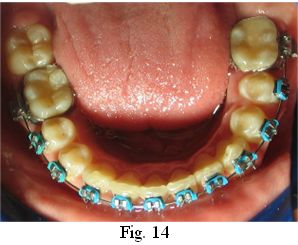

Este tratamiento integral consigue que, al mismo tiempo que se elimina el odontoma compuesto se restablezcan, el alineamiento dentario (Figs. 14-15), la coincidencia de las líneas medias y la correcta relación canina y molar (Figs. 16-17-18), mediante el uso de recursos ortodóncicos específicos, recuperando el equilibrio oclusal (25).